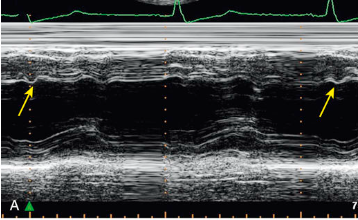

What is the arrow pointing to?

Constrictive pericarditis

What condition is this finding demonstrated in?